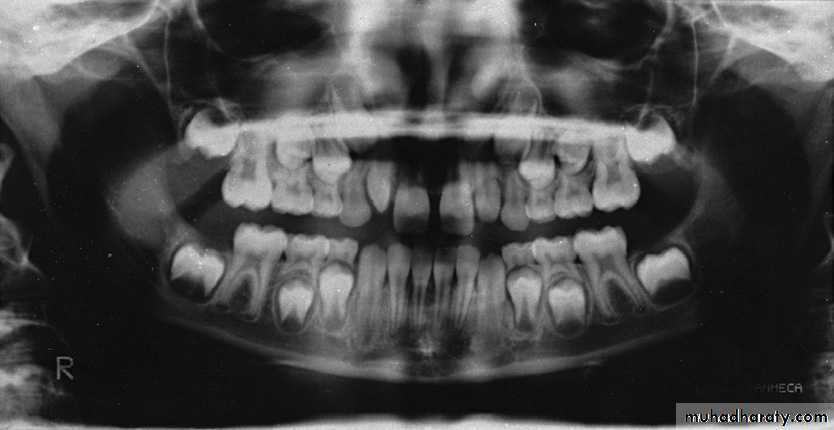

Panoramic is recommended at approximately the time of the early mixed dentition to assess

1. the dental age of the patient and

2. to aid in the early diagnosis of congenital and developmental anomalies.Panoramic radiograph

This child is 7-8 years old because he has the upper maxillar centrals erupted (depending on schedule of time of eruption of permanent teeth (eruption lecture)